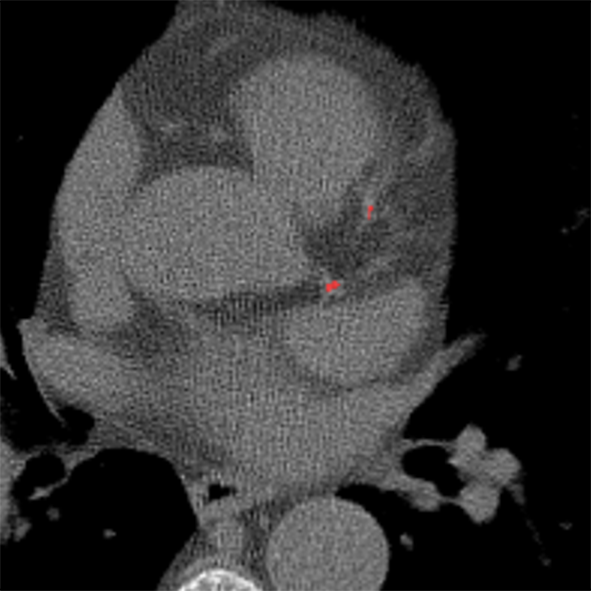

To establish a reference standard, calcifications were manually labeled in all scans. Scans were distributed among four trained observers and one radiologist with extensive experience in calcium scoring. To measure interobserver agreement, a subset of 100 scans (four scans from each of the 25 different scanner models and reconstruction algorithms) was annotated by two of the trained observers and the radiologist. Manual calcium annotation usually requires the observer to select only a single voxel per lesion. The lesion is then automatically segmented with region growing using the standard intensity threshold of . In low-dose scans, however, intensity based region growing often leads to large amounts of noise being segmented with the calcium (Figure 1). Moreover, it can lead to the spine and ribs being segmented together with calcium, or calcifications in arteries branching off the aorta being segmented together with calcium in the aorta. The observers therefore marked calcifications voxel-by-voxel () in the coronary arteries, the aorta and the aortic and mitral valves, including the annulus. Coronary calcifications were labeled as either left anterior descending artery (LAD), left circumflex artery (LCX) or right coronary artery (RCA). The left main coronary artery was considered part of LAD because these are difficult to distinguish on ungated scans. Motion artifacts caused by calcifications were annotated as calcifications because an exact separation of true calcification and artifact is often not possible. Depending on the amount of calcification and the image quality, the annotation effort varied from 5–10 minutes for images with soft reconstruction and little calcium to 60–90 minutes for images with sharp reconstruction and/or large amounts of calcium.

V-H Voxel-level vs. lesion-level annotation

The manual reference annotation was performed voxel-by-voxel to enable annotation of scans with poor image quality. To assess how much voxel-level annotation differs from the standard lesion-level annotation, we converted the voxel-level annotations into lesion-level annotations using 3D region growing with the standard calcium threshold (). Lesions were labeled using majority voting if they contained voxels with different labels. Scans with a more than five times increase in calcium volume were excluded. These were of the scans with soft reconstruction kernel and of the scans with sharp reconstruction kernel. In the remaining scans, the overall Agatston score increased on average by 85 in soft reconstructions and by 155 in sharp reconstructions. This clearly indicates that in low-dose CT scans, lesion-level annotation leads to an overestimation of the calcium score.